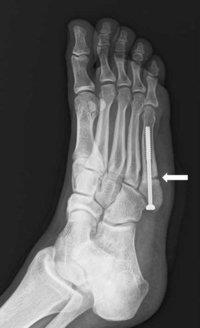

足の指の骨の根元をたどると中足骨(ちゅうそくこつ)という骨があります。これは親指側にある第1中足骨から小指側にある第5中足骨まで5本あります。ジョーンズ骨折とは第5中足骨の疲労骨折を指します。

手術は写真のように、特殊なスクリューを挿入する方法で行います。手術後はしばらくの間(3~4週間)骨折した足を地面に着けて歩けないため、松葉づえで歩かなければなりません。スポーツ活動への復帰時期は定期的にエックス線写真を撮影して骨癒合状態を評価しながら判断します。